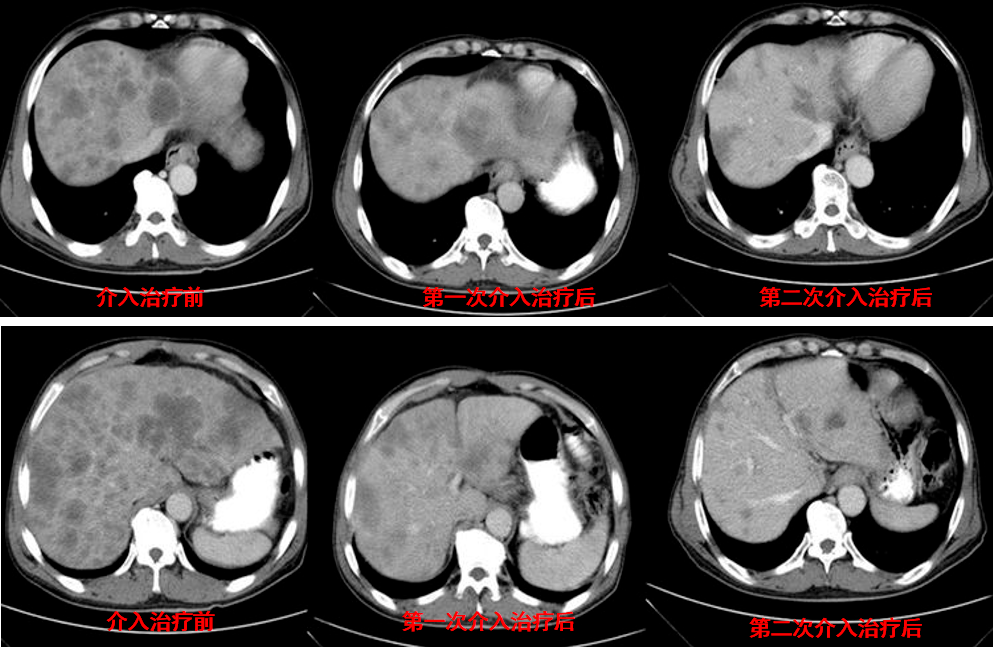

一例her2晚期胃癌肝转移病例的介入联合靶向治疗过程丨抗her之路 与妮

图片尺寸993x648